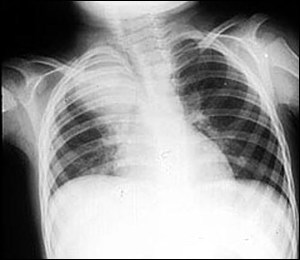

照片名称:正常胸片